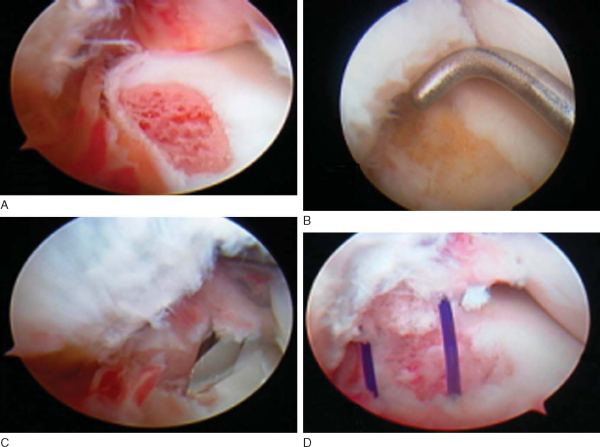

Meniscal tear repair by the RapidLoc system is illustrated in

Figure 46-1

.

Figure 46-1 |

The RapidLoc device is an absorbable anchor and suture device with a pre-tied slip knot to compress an absorbable top hat on the surface of the meniscus (see

Fig. 46-1

). The top hat is made from either PDS or polylactic acid; the suture options include Ethibond and slowly resorbing Panacryl. A single case applier is introduced with a 0-, 12, or 27-degree needle with the device loaded. The needle is advanced across the tear, as perpendicular as possible, to its silicone hub, limiting insertion depth to 13 mm. The handle on the applier is fired, which advances and deploys the backstop. The applier is removed. A knot pusher advances the pre-tied slip knot with top hat to the meniscus surface and allows variable tensioning across the tear.

In a study of the RapidLoc, we reviewed 75 meniscal repairs in patients who had undergone concomitant ACL reconstruction with a mean followup of 35 months. There was a 90.7% clinical success rate, similar to the equivalent group in the FasT-Fix study. Univariate analysis suggested that negative prognostic factors included a bucket-handle configuration, multiplanar morphologic features, tear length greater than 2 cm, and more than 3 months from tear to repair. Second-look arthroscopy in a small group showed healing and incorporation of the top hat into the meniscal tissue and no chondral abrasion, similar to the FasT-Fix study (

Fig. 46-6

).[23]

Figure 46-6 |